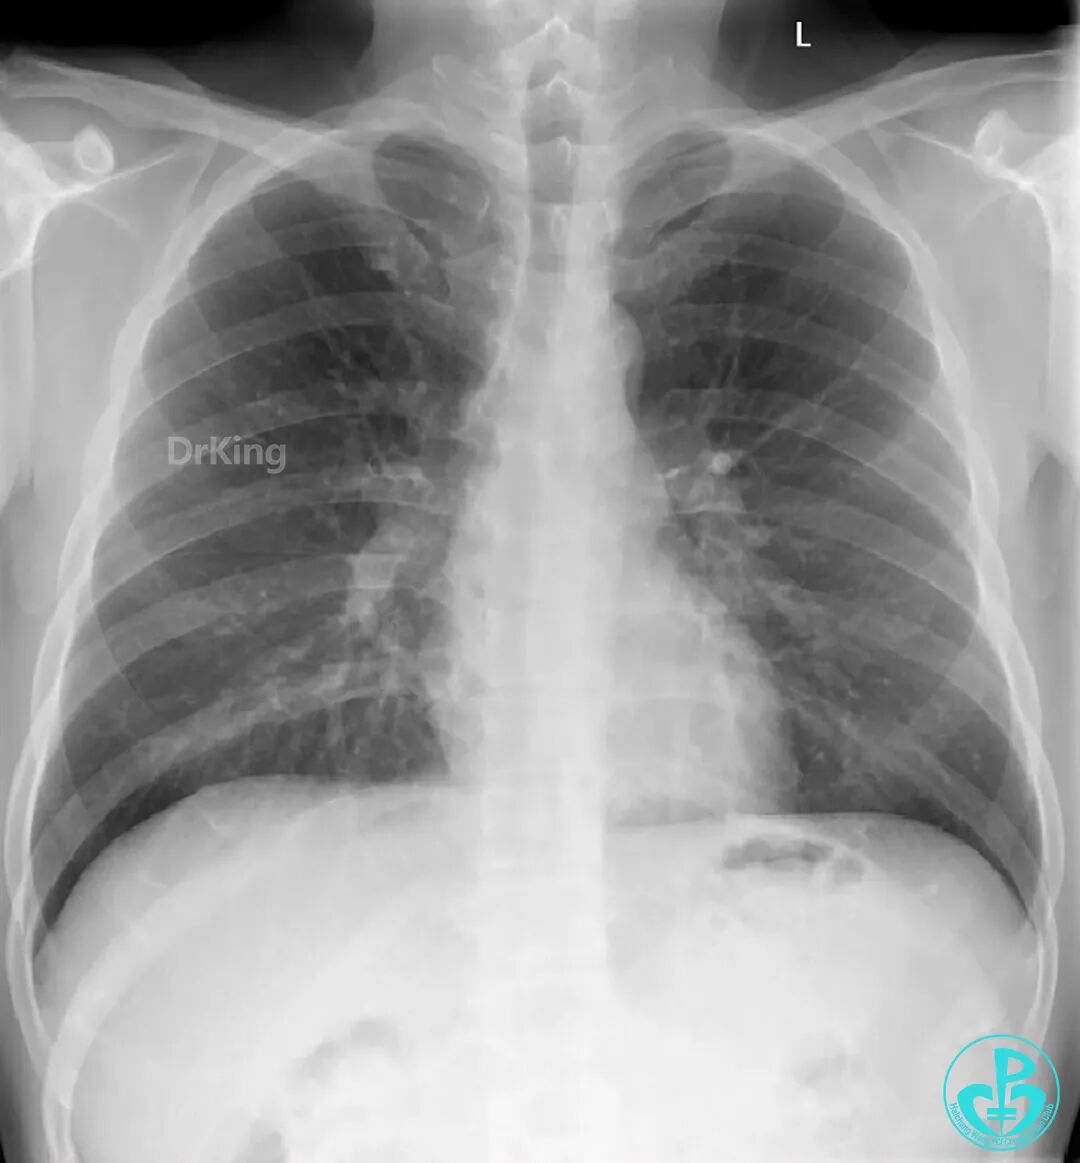

右冠脉支架通畅无狭窄,右冠脉给前降支远端提供逆向侧支循环。

EBU指引导管左冠脉造影显示粗大前降支中段闭塞,闭塞段近端有对角支发出,前降支同侧逆向显影,闭塞段不长。